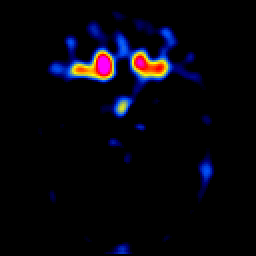

glioma overlay -- Slice #11

[Home][Help][Clinical] Slice 11